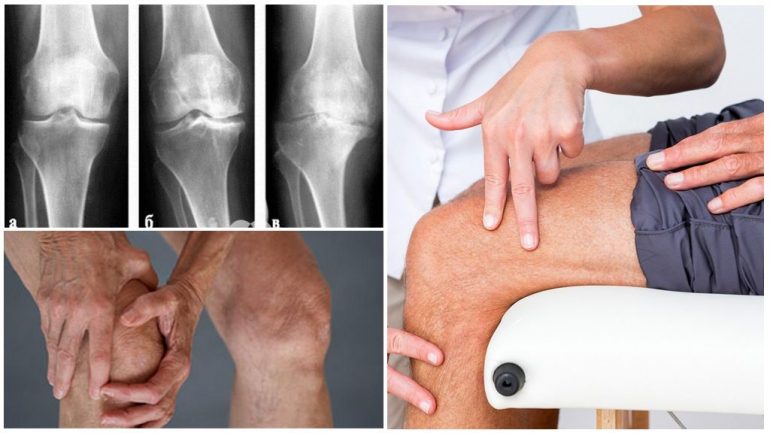

3-й ступінь гонартрозу можна вважати критичною стадією, коли суглоб переходить від відносно працездатного стану до значної втрати функції. Рентгенологічні зміни при цій стадії виражені помітніше, ніж при 2-й, але менш важкі, ніж при 4-й. Клінічна картина 3-го ступеня також суттєво відрізняється від ранніх етапів хвороби.

За Келгрен-Лоуренсом при гонартрозі 3-го ступеня на рентгені виявляють:

- помірне звуження суглобової щілини порівняно зі здоровим коліном;

- кістоподібні зміни поступово замінюються вогнищами остеосклерозу;

- дефекти кісткової тканини досягають близько 5 мм.

Рентгенологічні ознаки третього ступеня включають практично відсутню суглобову щілину, склероз суглобових поверхонь з вираженою деформацією та ділянками некрозу кістки під хрящем. По краях суглобових кінців кісток виявляються великі нарости й місця остеопорозу.